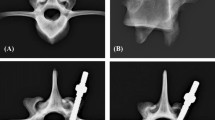

Six screw types were selected, each with two different outer diameters. All of them were approved pedicle screws in clinical use, with the exception of the screw type 5, which was a prototype (Königsee Implantate GmbH, Germany). The screws were made of titanium alloy and 45 mm long. The thread region of all screws is shown in Fig. 1. The outer diameter of the screws varied from 6 to 7.5 mm. All screws had a tapered core diameter, except type 6, which had a cylindrical core diameter. Thread pitch and core diameter were determined with a calliper gauge (Table 2). For screws with tapered core, the mean core diameter was determined by measuring each thread turn of the first 25 mm.